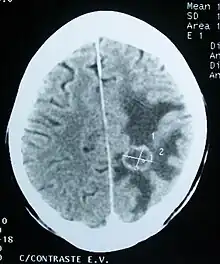

Imaging

Medical imaging plays a central role in the diagnosis of brain tumors. Early imaging methods – invasive and sometimes dangerous – such as pneumoencephalography and cerebral angiography have been abandoned in favor of non-invasive, high-resolution techniques, especially magnetic resonance imaging (MRI) and computed tomography (CT) scans,[38] though MRI is typically the reference standard used.[41] Neoplasms will often show as differently colored masses (also referred to as processes) in CT or MRI results.

- Benign brain tumors often show up as hypodense (darker than brain tissue) mass lesions on CT scans. On MRI, they appear either hypodense or isointense (same intensity as brain tissue) on T1-weighted scans, or hyperintense (brighter than brain tissue) on T2-weighted MRI, although the appearance is variable.

- Contrast agent uptake, sometimes in characteristic patterns, can be demonstrated on either CT or MRI scans in most malignant primary and metastatic brain tumors.

- Pressure areas where the brain tissue has been compressed by a tumor also appear hyperintense on T2-weighted scans and might indicate the presence of a diffuse neoplasm due to an unclear outline. Swelling around the tumor known as peritumoral edema can also show a similar result. This is because these tumors disrupt the normal functioning of the BBB and lead to an increase in its permeability.